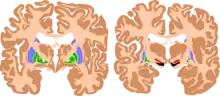

| The basal ganglia are instrumental in motor function. Damage to these areas may results in athetoid/ dyskinetic cerebral palsy (ADCP), or subtle movement disorders. | |